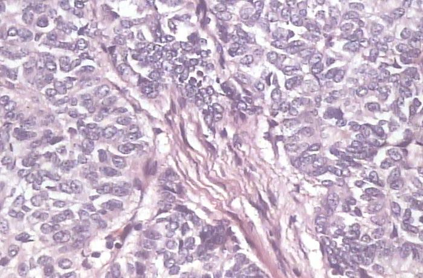

Background: Breast cancer has the highest prevalence in women globally. The classification and diagnosis of breast cancer and its histopathological images have always been a hot spot of clinical concern. In Computer-Aided Diagnosis (CAD), traditional classification models mostly use a single network to extract features, which has significant limitations. On the other hand, many networks are trained and optimized on patient-level datasets, ignoring the application of lower-level data labels. Method: This paper proposes a deep ensemble model based on image-level labels for the binary classification of benign and malignant lesions of breast histopathological images. First, the BreakHis dataset is randomly divided into a training, validation and test set. Then, data augmentation techniques are used to balance the number of benign and malignant samples. Thirdly, considering the performance of transfer learning and the complementarity between each network, VGG-16, Xception, Resnet-50, DenseNet-201 are selected as the base classifiers. Result: In the ensemble network model with accuracy as the weight, the image-level binary classification achieves an accuracy of $98.90\%$. In order to verify the capabilities of our method, the latest Transformer and Multilayer Perception (MLP) models have been experimentally compared on the same dataset. Our model wins with a $5\%-20\%$ advantage, emphasizing the ensemble model's far-reaching significance in classification tasks. Conclusion: This research focuses on improving the model's classification performance with an ensemble algorithm. Transfer learning plays an essential role in small datasets, improving training speed and accuracy. Our model has outperformed many existing approaches in accuracy, providing a method for the field of auxiliary medical diagnosis.